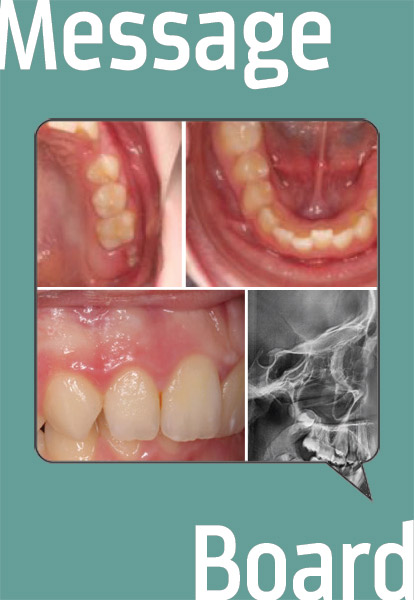

Townie "HappyOrthoD" has a young patient who could use treatment planning—and surgery could be an option. Is it called for in this case?